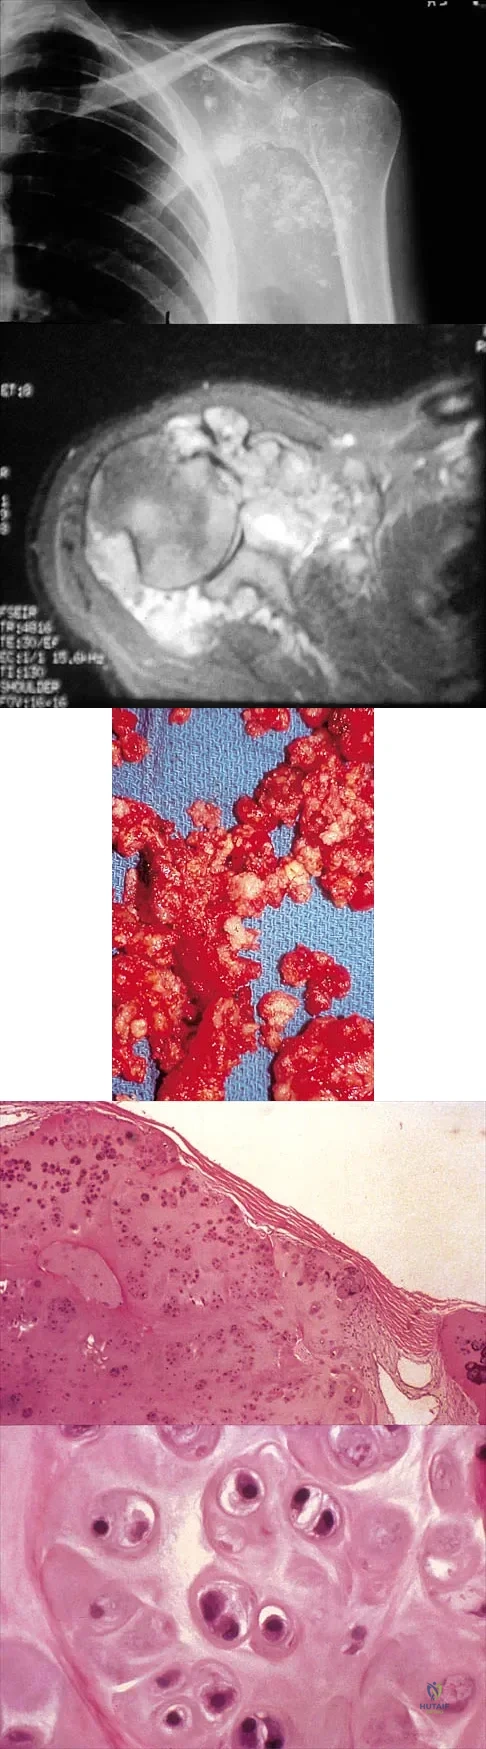

Question 35

A 32-year-old woman has had pain and a visibly growing mass in the shoulder for 3 years but denies any history of trauma. Examination reveals a swollen, boggy shoulder mass. The AP radiograph and MRI scan are shown in Figures 20a and 20b. Figures 20c through 20e show a portion of the excised mass and the photomicrographs of the biopsy specimen. What is the most likely diagnosis?

Explanation